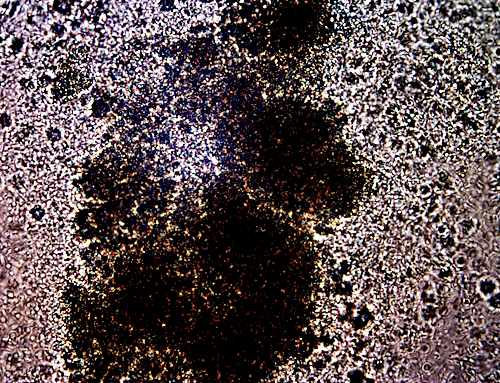

Drastic infusion level of and damage from synthetic biology (CDB) within the blood.

Massive deformation of cell integrity and geometry.

Unlikely that the cell can function in this state.

Original magnification approx. 3200x.

Blood damage documented in: THIS PAPER